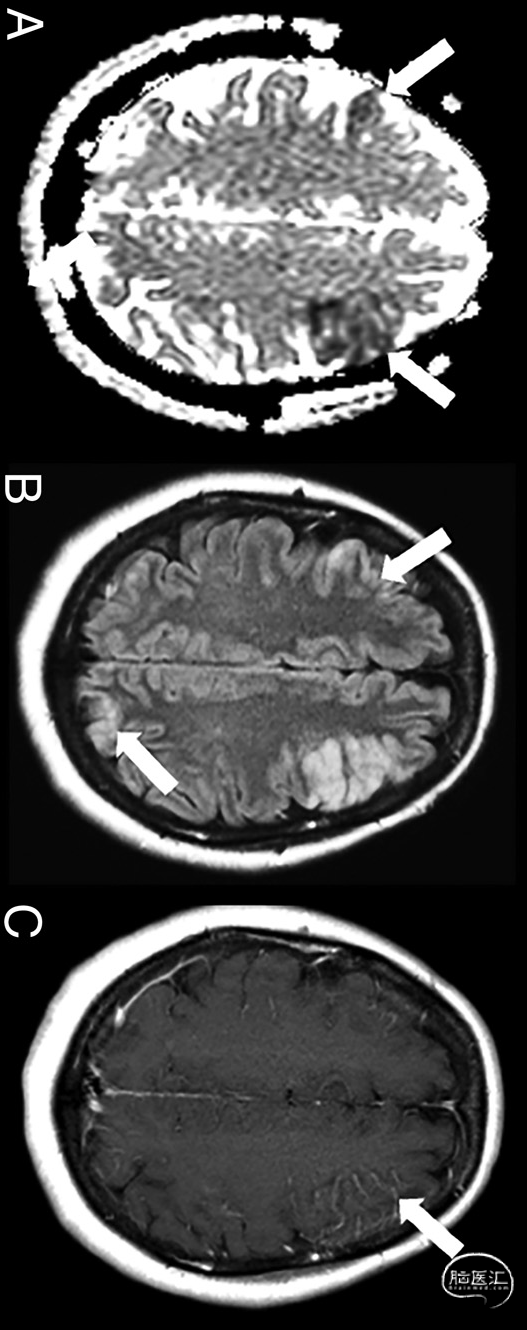

图3.女性,47岁,疑似CAE事件。增强脑MRI显示细胞毒性水肿(白色箭头,DWI序列,a)和血管源性水肿(白色箭号,T2-FLAIR序列,B)的混合模式,分布在整个大脑半球,主要分布在远端边缘带区域,沿左前ACA-MCA交界区可见软脑膜增强(白色箭头号,对比后[MultiHance;Bracco Diagnostics]2D spin-echo T1序列,C)。CAE与腹腔镜注入气体相关,导致血管内进入气体: